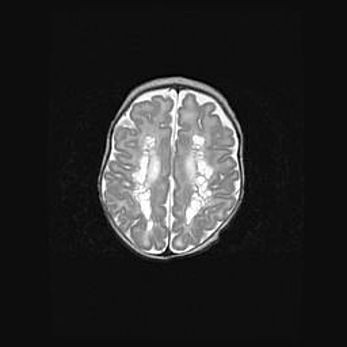

Множественные кисты обоих полушарий головного мозга, наибольшая из них в правой затылочной области. Ассиметричная атрофическая гидроцефалия.

Возраст: 7 месяцев

Вес: 5660 г

Пол: мужской

Окружность головы: 41,5 см

Срок гестации: 28-29 недель

Кисты головного мозга развиваются в результате многоочаговых некрозов вещества мозга и возникают вследствие перенесенной перинатальной инфекции, менингитов, энцефалитов, асфиксии, родовой травмы, расстройств мозгового кровообращения различного генеза. Образованию кист в веществе головного мозга плодов и новорожденных способствуют такие факторы, как высокое содержание в нем воды, недостаточная (или отсутствие) миелинизация и слабая астроглиальная реакция на повреждение.

Кисты могут сочетаться с гидроцефалией и другими поражениями головного мозга.